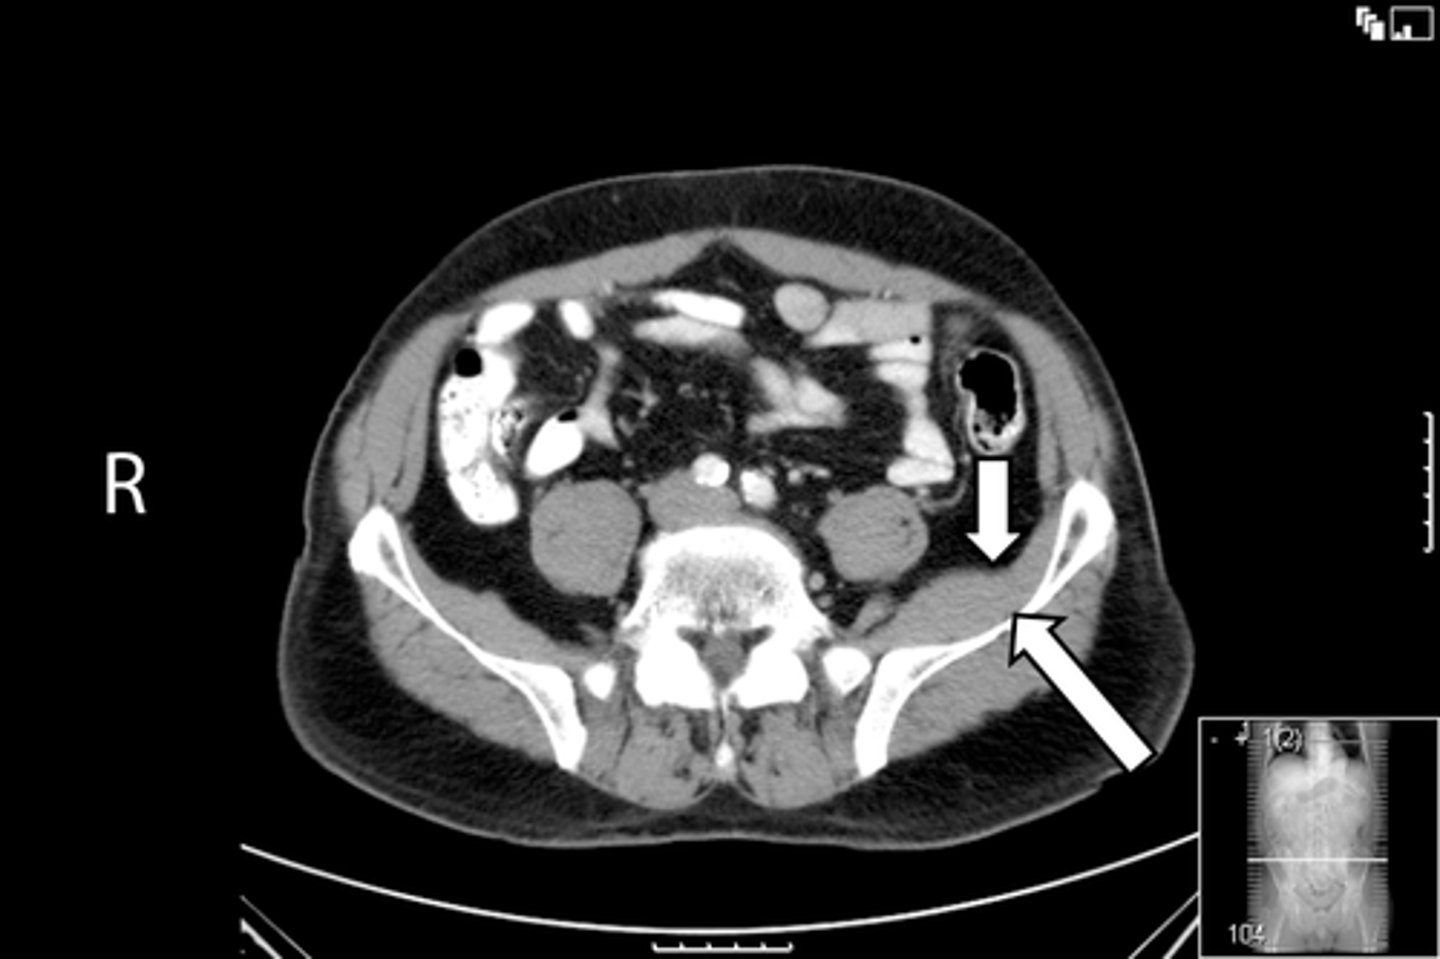

Axial bony pelvis CT

What is the image?

38

L acetabulum

<p>What is indicated in the image?</p>

New cards

What is indicated in the image?

40

L piriformis muscle

42

R piriformis muscle

44

Sacrum